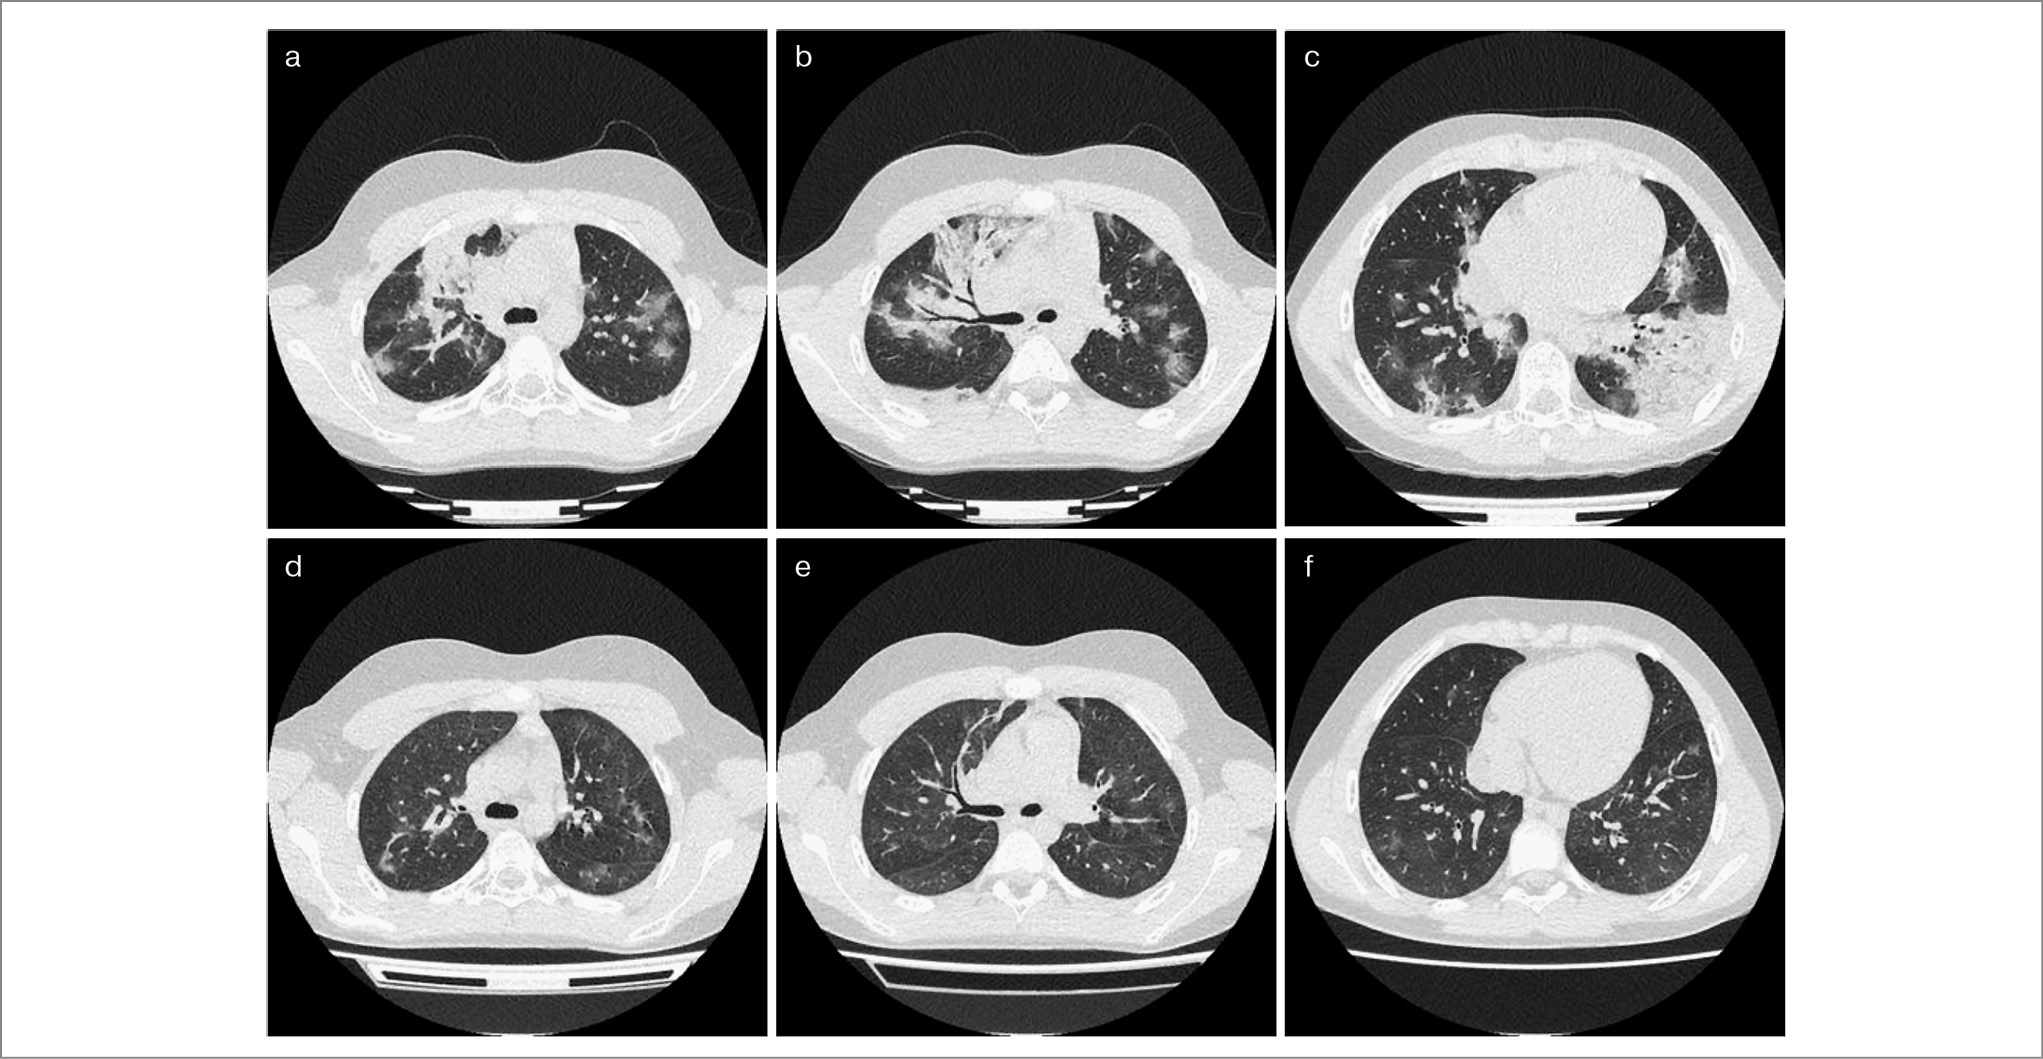

КТ-проявления COVID-19. По имеющимся данным, КТ грудной клетки может демонстрировать различные особенности визуализации или паттерны у пациентов с COVID-19 с различным временным течением и тяжестью заболевания [19, 20].

Начальными проявлениями в первые дни заболевания служат многочисленные двусторонние периферические (субплевральные) уплотнения легочной ткани по типу «матового стекла», в том числе в сочетании с консолидацией и/или с симптомом «булыжной мостовой» (симптомом «лоскутного одеяла»), многочисленные двусторонние округлые участки уплотнения по типу «матового стекла» и консолидации в сочетании с симптомом «обратного ореола» (симптомом «атолла»); рис. 3 [21].

Рис. 3. Пациент 12 лет со среднетяжелым течением COVID-19: а, b, с – на 5-й день заболевания, двусторонние участки поражения по типу «матового стекла», участки консолидации вдоль плевры, cуммарная площадь поражения легких около 75%; d, e, f – на 11-й день заболевания, мультилобарные двусторонние участки уплотнения легочной паренхимы по типу «матового стекла» с локальными участками консолидации, площадь поражения легочной паренхимы – 50%. Из личного архива авторов А.Б. Малахова, Т.А. Гутырчик.

КТ-поражения, характерные для вируса гриппа. По данным зарубежной литературы, наиболее характерными поражениями легких, выявляемыми на КТ ОГК у больных гриппом, являются сочетание «матового стекла» и уплотнение воздушного пространства с пятнистым рисунком и преобладанием в нижних/средних отделах, причем изменения чаще всего носят двусторонний характер. Так, в исследовании E. Karadeli и соавт., проведенном во время пандемии гриппа (H1N1), самым часто выявляемым изменением на КТ ОГК явилось двустороннее поражение легких (80% больных). Наиболее распространенной находкой было сочетание участков уплотнения интерстиция по типу «матового стекла» и уплотнения воздушного пространства. Вовлечение в процесс нижних и периферических отделов имело место у 89% пациентов [22].